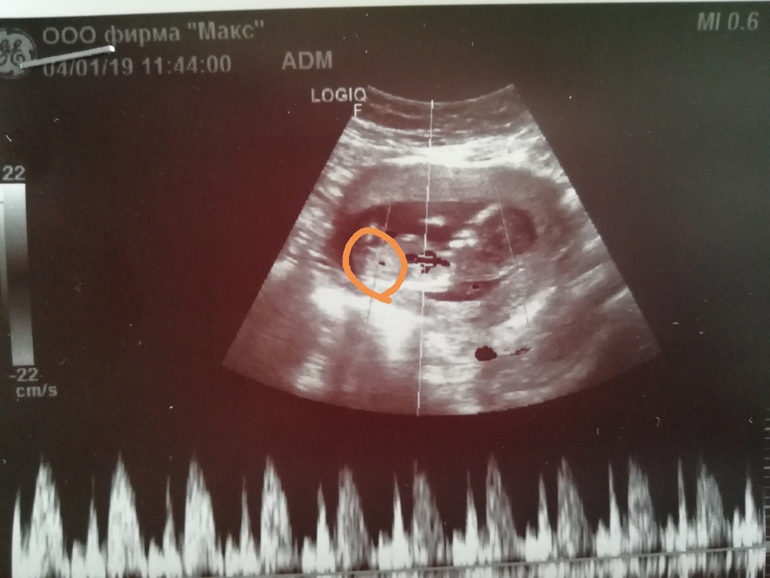

Вот мой детёныш на 13 й недельке😃

Это не он?

Если бугорок, обведенный Вами кружочком и есть половой бугорок, то это девочковый пирожок. Пусть Ваши желания исполнятся.

Тут сомнительно пока. У меня со старшим сыном прям вверх пипка уверенно торчала, без сомнений было. Со вторым сыном были сомнения у врача, сейчас на 90% девочка, но половой бугорок смотрит вниз. Тут тоже вроде угол девчачий, но я почему-то в сомнениях, бугорок ли это.